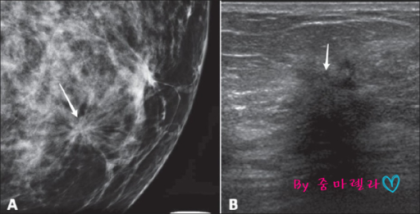

송탄의 유방암 검진은 일반적으로 유방조영술로 시행하는데, 유방조영술은 유방압박 후 유방의 상하, 유방의 내부와 외부를 엑스레이로 검사하는 것입니다. 암 여부를 구분할 수 있다고 합니다. 맘모톰 촬영 후 검사 결과지를 받아보실 수 있습니다. 병원에 가서 검사를 받는 것이 가장 좋습니다. 일반적인 치밀유방의 경우 유방조영술을 통해 얻을 수 있는 정보가 제한적이기 때문에 이 경우에도 유방초음파검사를 통해 유방초음파에 이상이 있는지 등을 추가로 시행하는 것이 좋습니다. 낭종. 혹의 모양과 카테터의 변화를 자세히 관찰할 수 있고 인체에 무해하며 젊은 환자와 임산부가 언제든지 확인할 수 있다는 장점이 있다. 초음파를 단독으로 사용하는 것이 대체 불가능한지 물으셨습니다. 고위험군이거나 40세 이상의 여성이라면 미세석회화, 종양, 구조적 뒤틀림을 찾기 위해 두 가지 검사를 동시에 받는 것이 최선이라고 해석합니다. 송탄유방암검진을 통해 조직검사가 필요한 경우 조직이 악성인지를 판단하는 것이 매우 중요하기 때문에 빠르고 안전한 유방암 검진을 위해 전체생검과 맘모톰을 이용합니다. 병변의 삽입과 제거는 국소마취 하에 이루어지기 때문에 통증에 대한 부담이 적고 흉터가 거의 남지 않아 환자가 크게 걱정하지 않고 검사를 받을 수 있다. 유방질환 치료에 적합하도록 종양을 제거할 수 있으나 맘모톰 수술 전에 정확한 검사가 이루어져야 합니다. 유방조영술 또는 유방조영술은 악성일 수 있거나 크기와 수가 증가한 종양을 확인하는 데 사용할 수 있습니다. 통증이 있거나 겉으로 보이는 종양이 있는지 주의 깊게 검사한 후 맘모톰 수술을 시행합니다. 국가건강검진을 시행하는 병원이 조직검사와 같은 정밀검사를 할 수 없는 곳이라면 검사결과와 발급된 유방조영상 데이터를 가지고 유방전문센터로 가기가 번거로울 것이다. 원스톱으로 진행되는 MRI 검사도 가능하며, 환자가 이미 검사 데이터를 가지고 있다면 정확한 진단에 도움이 되며, 같은 검사를 반복할 필요가 없으므로 휴대하는 것이 좋습니다. , 유방암은 다른 암과 달리 다양한 치료를 통해 잠재력이 크며 생존율이 높지만 앞으로 암의 수가 증가할 것으로 예상되므로 유방암은 고위험군과 같은 관리 가능한 질병으로 전환될 것으로 예상됩니다. 혈압, 당뇨병 등 앞으로 가장 중요한 것은 조기에 진단하고 치료를 시작하는 것입니다. 유방암을 예방하는 가장 효과적인 방법은 정기적인 유방암 검진이라고 할 수 있습니다 지속적인 치료가 필요한 병원을 선택하더라도 신중한 분들에게 건강한 유방수술은 너무 오래 기다릴 필요 없이 바로 확인할 수 있습니다 . 조직검사가 필요한 경우 당일 검사가 가능하도록 대학병원급 의료장비로 유방암 진단 시 정확한 검사를 시행할 수 있도록 최선을 다하겠습니다. 최근에는 환자의 연령이 점점 젊어지고 재발률도 높기 때문에 정기적인 검사만이 최선의 방법입니다. 오랜 진료 경력의 민러지 원장님께서 직접 검진부터 치료까지 1:1 맞춤 진료를 진행하고 있으니 송탄 유방암 검진 외에도 갑상선 검진도 진행해보시길 바랍니다! 광고 후에 계속하십시오. 다음 주제저작자 취소 건강한 유수술 재생 0 좋아요 0 좋아요 공유 0:00:00 재생 음소거 00:00 00:00 라이브 전체 화면 해상도 설정 currentTrack 자막 비활성화 재생 속도 NaNx 해상도 자막 설정 비활성화 옵션 글꼴 크기 배경색 재생 속도 0.5 x 1.0x(기본값) 1.5x 2.0x 알 수 없는 오류가 발생했습니다. 도움말 보기 음소거되었습니다. HD로 재생하려면 이 동영상에 라이선스를 부여하세요. 설정에서 해상도를 변경해 보세요. 더 알아보기 0:00:00 Collapse/ExpandHealthyBreastSurgery #HealthyBreastSurgery (이 게시물은 HealthyBreastSurgery에서 작성했습니다.)